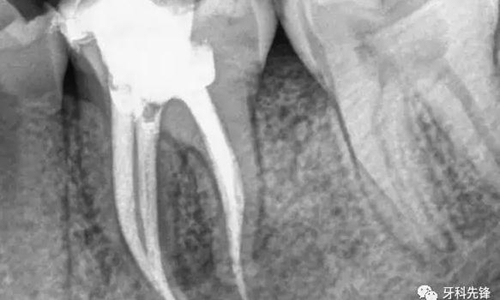

當(dāng)牙齒做完根管治療,由于牙齒自身的結(jié)構(gòu)及治療的需要,牙冠中心一般都是空的,這時(shí),如果直接做牙套,其抗折斷力很差,一般都需要在牙根上打上樁釘,做出個(gè)結(jié)實(shí)的核,以對(duì)抗牙齒使用中的折斷力。

對(duì)于后牙來說,做完根管治療之后一定要做上牙冠,否則在承受咬合力量時(shí),牙齒容易出現(xiàn)斷裂。少數(shù)做完根管治療的后牙,若是要做單一的牙冠,只需將所剩牙質(zhì)修補(bǔ)足夠,則可不需做樁釘,但若做完根管治療的后牙是要作為假牙的基牙,則無論牙質(zhì)所剩多少,最后都能做好樁釘。